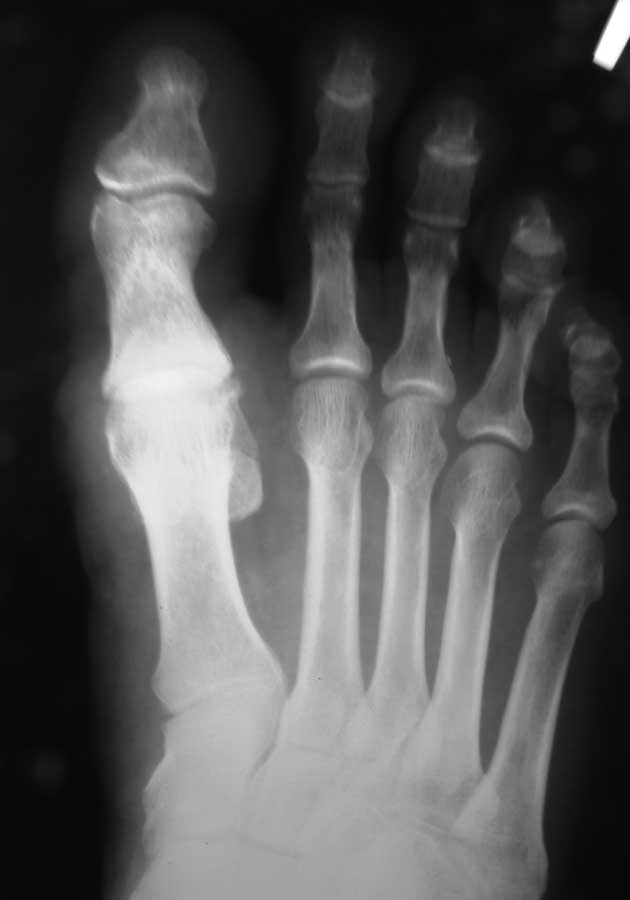

Здравствуйте, коллеги. Помогите с тактикой дальнейшего лечения.Мужчина 52 года, активный

физически. В марте 2012 оперирован по поводу ДОА плюсне-фалангового сустава 1 пальца,

сделана резекция основания основной фаланги и остеофитов головки плюсневой кости.

Послеоперационное лечение: массаж, физиотерапия. В настоящее время беспокоят сильные

боли в суставе, сохраняется ограничение движений. Дальнейшая тактика: артродез ПФС?,

Эндопротезирование ПФС?, повторная резекция основной фаланги? Мнения наших коллег

разделились. На фотографиях: вид стопы в настоящее время, рентгенограммы до операции,

после операции, в настоящее время. Прошу прощения за неважное качество снимков.